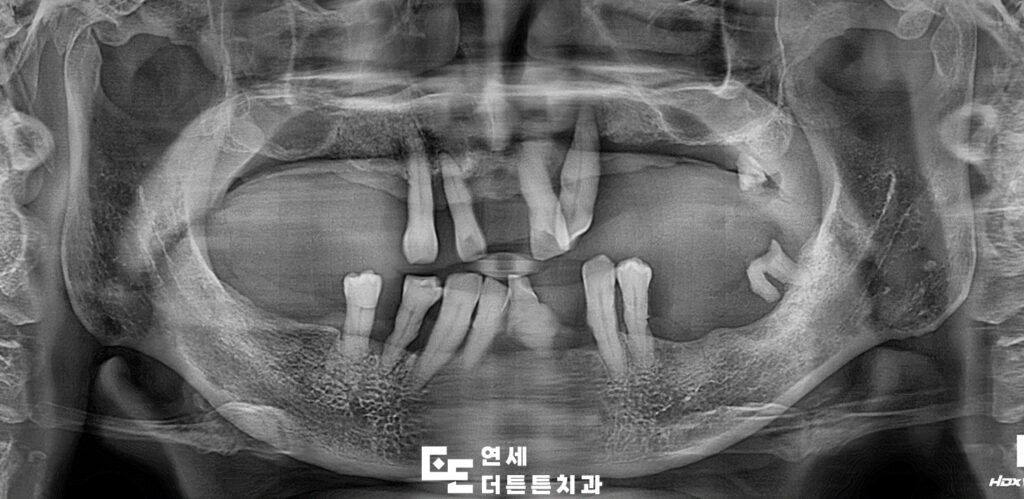

환자분의 사진을 보시면

오랜 기간 진행된 치주염으로 인해

잇몸뼈가 많이 녹아 있고 뿌리만 남아 있는

치아들도 곳곳에서 관찰되고 있었는데요.

정상적인 치아의 뿌리는 잇몸에

담겨 있는 것처럼 뼈 깊숙이 고정되어 있는데요.

환자분의 경우에는 뿌리를 잡고 있는

잇몸뼈가 거의 다 녹아 치아가 많이 흔들리고

상태가 좋지 않았습니다.